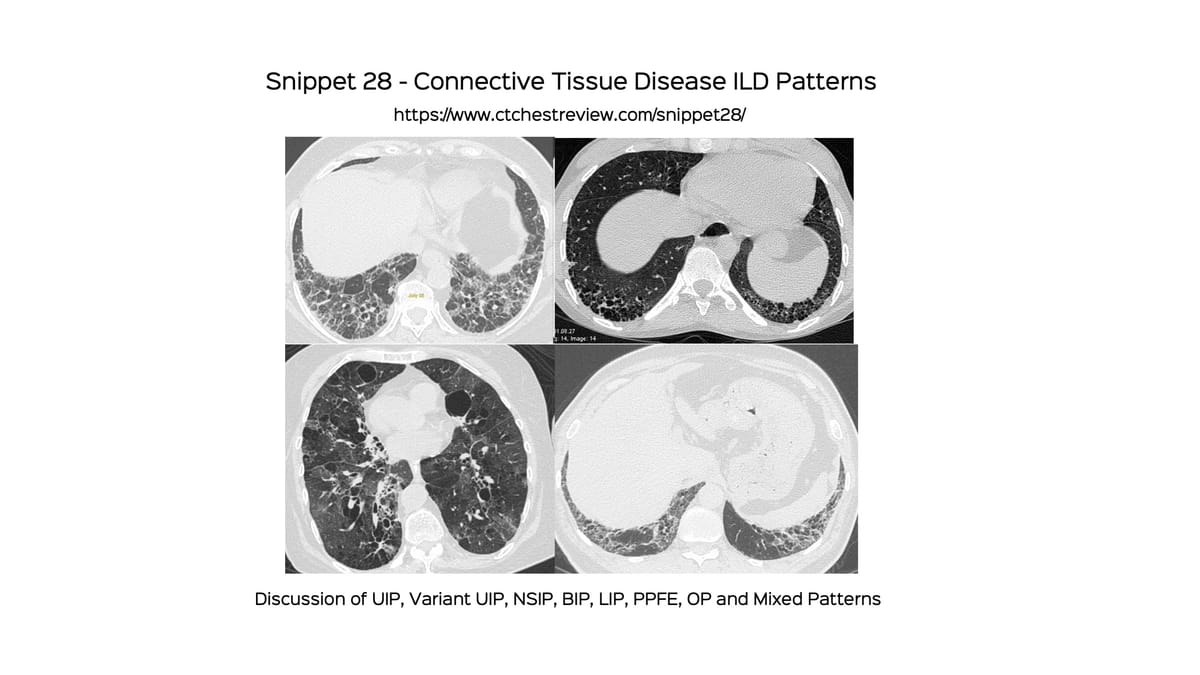

Case of the Day 116 - Mixed Patterns in Connective Tissue Disease ILDs

Mixed patterns are increasingly being recognized in CTD ILDs and should be mentioned in the report.

This complements the previous post on Connective Tissue Disease ILD Patterns, where I did not discuss "mixed patterns" in detail.